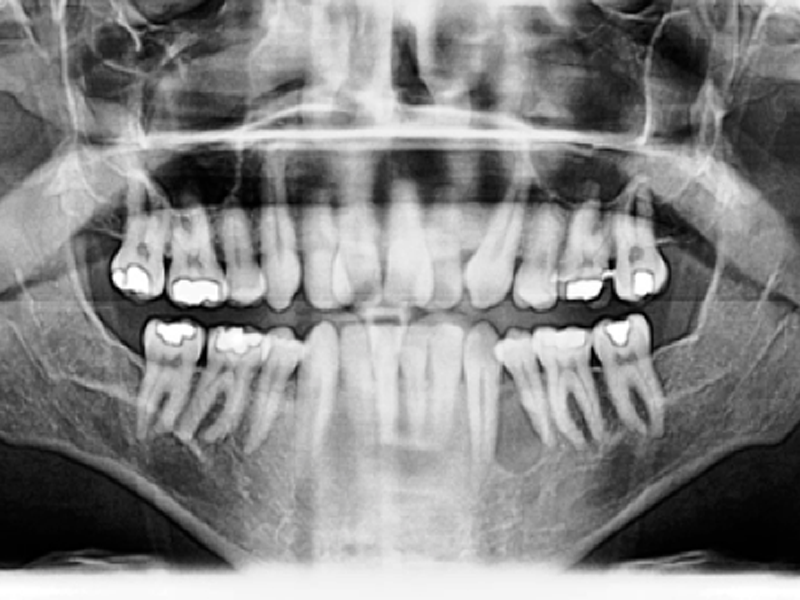

IV Sedation Wisdom Teeth Pembroke Pines | Complications with Impacted Wisdom Teeth